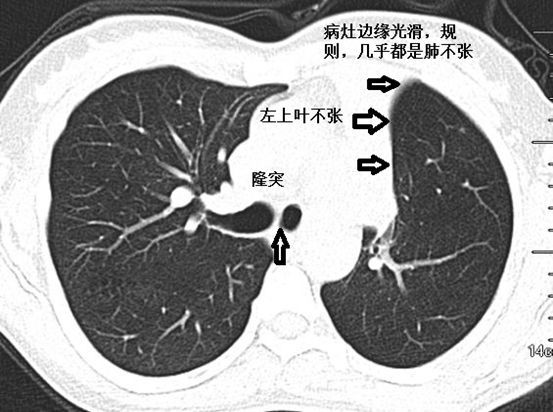

肺不张ct读片太难看完这篇文章轻松入门

肺不张影像图